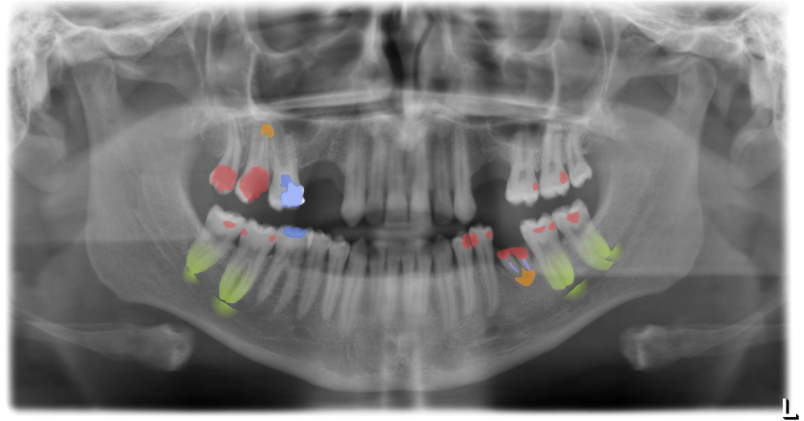

The software detects caries, periapical radiolucencies, periodontal bone loss and infections, but also implants, root canal fillings and dental restorations with reliably high quality. The findings are highlighted in color for improved patient communication and the software automatically generates a report, saving valuable time.

The integrated tooling allows the user to switch back and forth between the native X-ray image and the color-highlighted detections. This also makes it easy for the patient to understand the problem and the treatment plan.